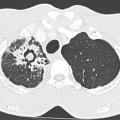

Goitre plongeant

Image